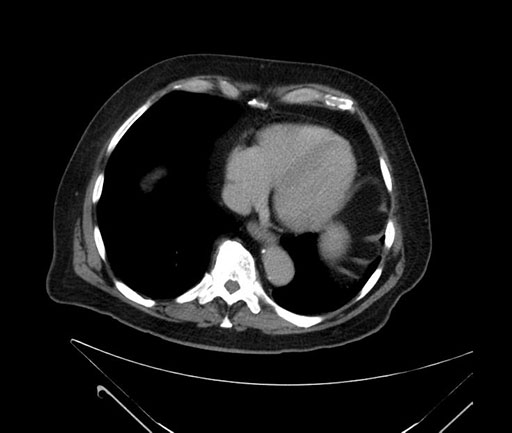

Coronal - stented